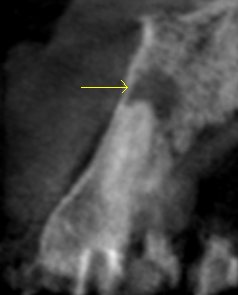

術前の問題歯の立て切りCT画像。根っこの先に膿の袋(黒い部分、黄色い矢印)がある。